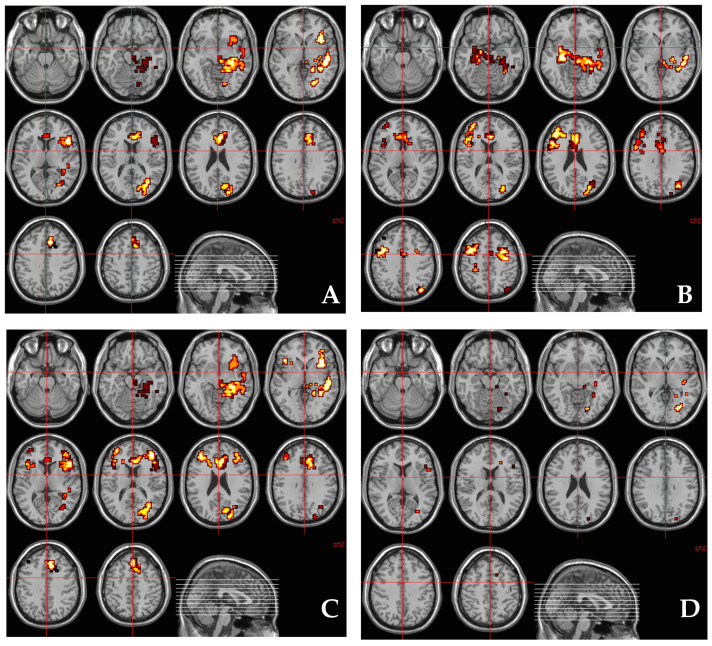

There was a statistically significant effect of THC administration on the normal pattern of regional brain activation associated with fear in a distributed network of regions including the left parahippocampal gyrus and amydgala. THC enhanced left parahippocampal gyrus/amydgala engagement while viewing fearful faces compared to neutral faces, while there was an attenuation of engagement in these regions under placebo while viewing fearful faces relative to neutral faces (Figure 1).

3.4. Relationship between AKT1 Genotype (rs1130233) and the Effect of THC on Regional Brain Activation during Fear Processing

There was a statistically significant association between the effect of THC on regional brain activation while processing fear and AKT1 genotype (rs1130233), such that the higher the number of risk alleles (A) the greater was the effect of THC on fear-related brain activation across a network of brain regions (Figure 2A and Table 3) that included parahippocampal, fusiform and cingulate gyri. Additionally, a cluster in the left anterior cingulate gyrus/medial prefrontal cortex (x = −11, y = 26, z = 26; rho = 0.395, p = 0.021) correlated positively with change in STAI scores.

3.5. Relationship between Methylation at CpG11–12 Site around AKT1 SNP (rs1130233) and the Effect of THC on Regional Brain Activation during Fear Processing

There was a significant association between the effect of THC on regional brain activation while processing fear, and methylation at CpG11–12 site, such that the higher the percentage of methylation at this site, the greater was the effect of THC on fear-related brain activation across a network of brain regions (Figure 2B and Table 4) that included parahippocampal and cingulate gyri. Anxiety induced under the influence of THC (indexed using STAI) correlated positively with its effect on parahippocampal activation (x = 29, y = −22, z = −13; rho= 0.401, p = 0.017).

3.7. Relationship between AKT1 Genotype (rs1130233) and the Effect of THC on Regional Brain Activation during Fear Processing after Covarying for Methylation at CpG11–12 Site

On investigating whether the association between AKT1 rs1130233 genotype and THC-induced change in brain activation while processing fear was mediated by degree of methylation at the CpG11–12 site, we found that some of the association between AKT1 rs1130233 polymorphism and effect of THC on fear-related brain activation (as depicted in Figure 2A and Table 1) was no longer present (as depicted in Figure 2C and Table 5) after covarying for percentage methylation at the CpG11–12 site. This suggested that methylation percentage at the CpG11–12 site partly mediated some of the association between AKT1 rs1130233 polymorphism and the effect of THC on fear-related brain activation. Brain regions where the association between AKT1 rs1130233 genotype and THC’s effect on fear-related activation were mediated by percentage methylation at the CpG11–12 site around AKT1 rs1130233 localize to the left parahippocampal gyrus extending toward the lingual gyrus, left fusiform gyrus, midbrain extending to the left parahippocampal gyrus, left hippocampus extending towards the insula and the left superior temporal gyrus (Figure 2D and Table 6).